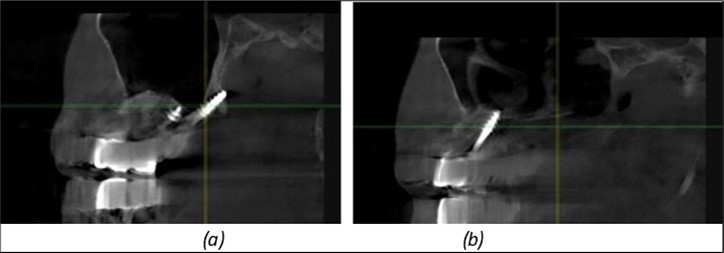

Figure 11.Implants in the anterior area anchored in the nasal cortex (BCS and TPG): (a), (c) – BCS implants fixed in the nasal cortex; (b), (d) – TPG implants fixed in the second nasal cortex with compression in the trabecular area.

Figure 12.Implants fixed distally in quadrant 4 with fixation at the level of the mylohyoid line: (a) The most distal implant fixed in unaffected bone from the previous restoration; (b) The implant fixed in the area where the two stage implant was removed.